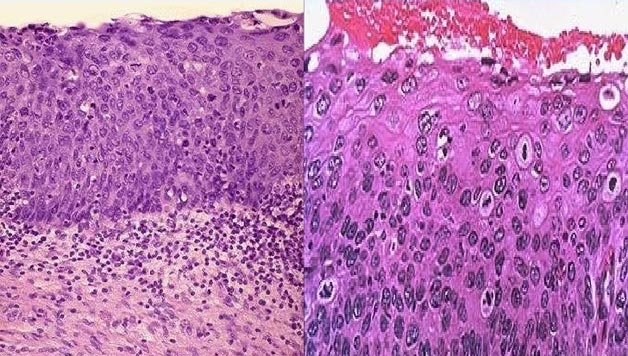

Fisioterapeutak modan gaude; artikuluak, txostenak, elkarrizketak, hitzaldiak… Pixkanaka presentzia handiagoa dugu gizartean eta, orain arte ez bezala, masajea eta beste terapia fisikoen eskari handia unibertsitatetik irtendako profesional egokiekin asez doa. Hala ere, nahiz eta denok gure izena bolo-bolo darabilten, benetan egiten duguna ez da hain ezaguna. Norbaiti gure eguneroko lana zein den galdetuz gero, inor gutxik aipatuko dizu ezer masajeetatik, elektroterapiatik eta ultrasoinuetatik aparte. Emakumearen bizitzan, garrantzi handia du hormona ekoizpenak, izan ere, honek markatuko du noiz hasi eta amaitzen den bere ernalkortasuna. Ginekologia arazoak edonoiz ager daitezkeen arren, haurduntza eta erditzean askoz ere sarriago gertatzen dira. Umea kanpora ateratzeko egin behar izaten diren esfortzuen ondorioz, pelbis hezurra azpitik ixten duen periné edo estalki muskulu-fibrosoa eten egiten da; puntu famatuak eman ondoren, orbain bihurtuko dira. Gainera, erditzean konplikazioak egon badira (oso erditze luzeak, haurrak pasatzeko lekurik ez, kirurgia edo instrumentala erabili beharra… ), azaleko giharretako arazoez aparte, zauri sakonak ere egon daitezke: zesareak, uteroa posizio txarrean geratzea, erraiak elkarri pegatzea, pelbis eta sakro hezurren desorekak…